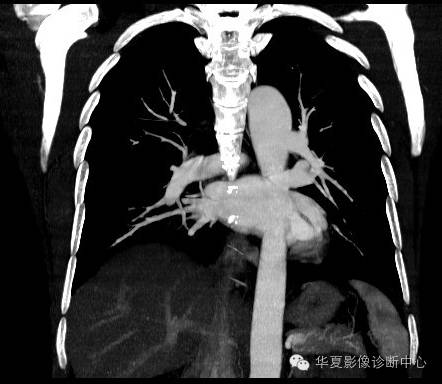

| 影像表现及分析: | 影像表现:定位左下叶;左下叶体积缩小,整体密度增高,支气管分布正常,其内见血管增多,但是走形正常,未见杂乱、迂曲的血管影;血管连向肺门下方软组织密度结节灶,结节与主动脉分界不清,增强后,见降主动脉发出异常粗大血管供血整个左下叶,左下肺动脉细小。 |

| 确诊依据: | CTA明确左下叶供血动脉为降主动脉发出 |

异常体动脉供应正常下肺基底段完整含义为起源于降主动脉的异常动脉供应下肺基底段,而基底段支气管树和肺实质正常,同时基底段肺动脉缺如或狭窄【大部分缺如(完全型),部分狭窄(不完全型)】;95%以上累及左下肺,因此也称为异常体动脉供应正常左下肺基底段。 病因尚未明确,可能是胚胎发育时期供应肺芽的背主动脉原始小分支退化不全,与肺实质形成异常连接,并影响肺动脉与肺血管床连接而导致此部位肺动脉发育不良,而支气管、肺组织的发育未受影响。本病的病理生理基础为左向左的分流,体动脉供应的肺组织充血,体循环的高压可增加肺血管床的压力和左心负荷,同时也增加肺循环量和压力而增加右心负荷,导致各种临床症群。本病可无临床症状,部分患者可有咯血、呼吸道感染、呼吸困难、充血性心力衰竭。 影像表现:左肺下叶体积缩小,整体密度稍增高,支气管树走形、分布正常,血管增多、稍增粗;增强后显示左下肺动脉幼小,甚至不发育;下叶由主动脉发出的粗大血管供血。 |